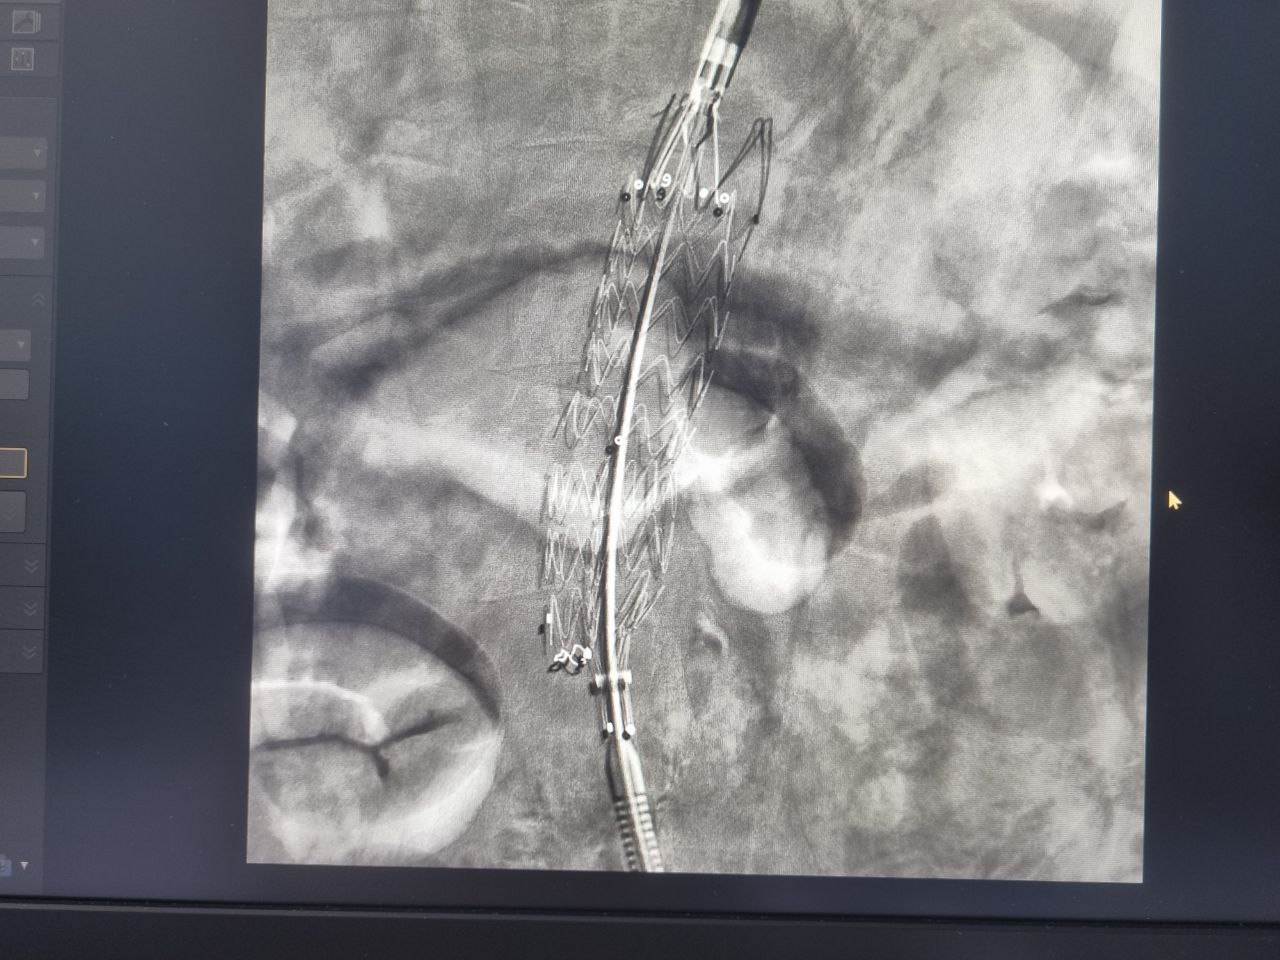

После тщательного обследования в ходе ангиографического исследования у пациента были обнаружены признаки нестабильности в просвете аневризмы, а также критическое поражение устья левой почечной артерии, вовлеченное в аневризму брюшной аорты.

Коллегиально специалистами больницы было принято решение провести эндопротезирование брюшного отдела аорты с переходом на подвздошные артерии и стентирование левой почечной артерии при помощи эндоваскулярного пособия. Чтобы снизить риск угроза разрыва и внезапной смерти.

«Одной из альтернатив открытых хирургических операций для лечения аневризмы аорты на данный момент является эндоваскулярное протезирование с установкой в зоне аневризмы стент-графта (металлической сетки, покрытой изнутри полимерной тканью). Такая конструкция создает каркас внутри сосуда и предотвращает риск разрыва аневризмы», - говорит Игорь Борисович.

«После операции у пациента произошла эпителизация металлического каркаса стентов и усиление стенки сосуда при сохранении диаметра артерии», - поделился врач.